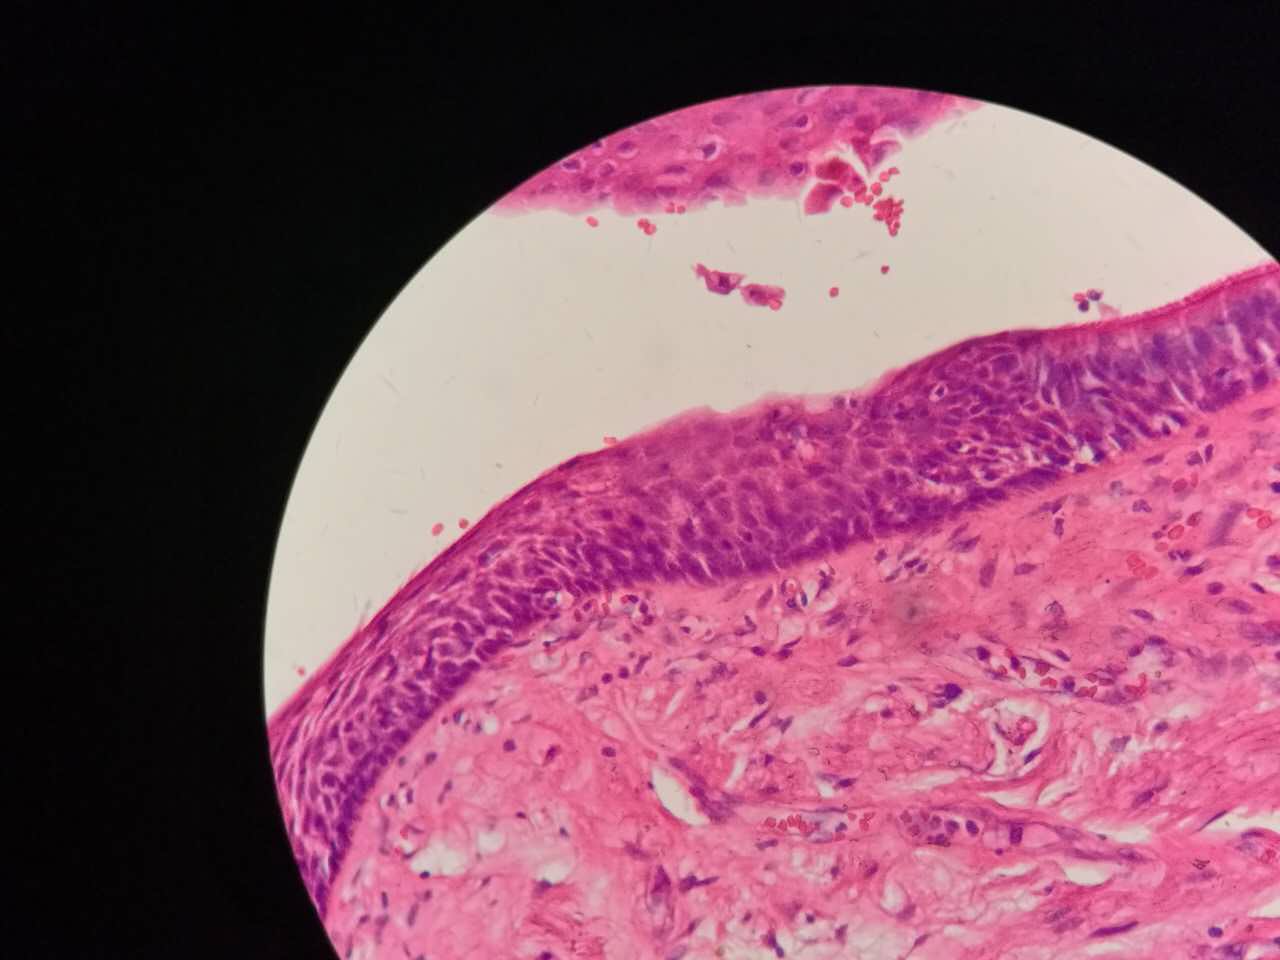

支气管柱状上皮鳞状化生

鳞状化生

支气管粘膜鳞癌

结构紊乱,细胞异型

支气管鳞癌

复层排列,细胞有很多层

基底侧边界清楚

鳞癌生长,呈巢团状

巢团边界大多清楚

巢团可以很大,中央血供不足,就会坏死

中央红色的,有碎核

这个鳞癌不是早期

坏死也可以很大

较大的粉红区都是坏死,可以看出坏死是因为巢团大,中央坏死

鳞癌是从支气管鳞化,异型增生,癌变,浸润,这么发展过来的。强调!

这个下面的软骨说明了是大气管,中央型